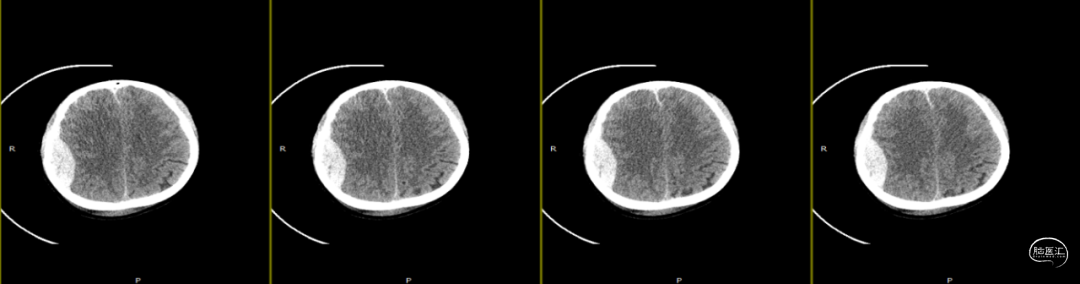

2024-07-21 08:58:55术后58天复查(如上图)。

术后58天颅脑磁共振平扫(如上图):右侧额顶颞部见斑片状异常信号,呈片状T1WI低、T2WI稍高信号影,T2FLAIR呈稍高信号,边界清,右侧额顶颞叶脑组织受压,DWI(b=1000)呈混杂高信号,相应ADC呈混杂高信号影。